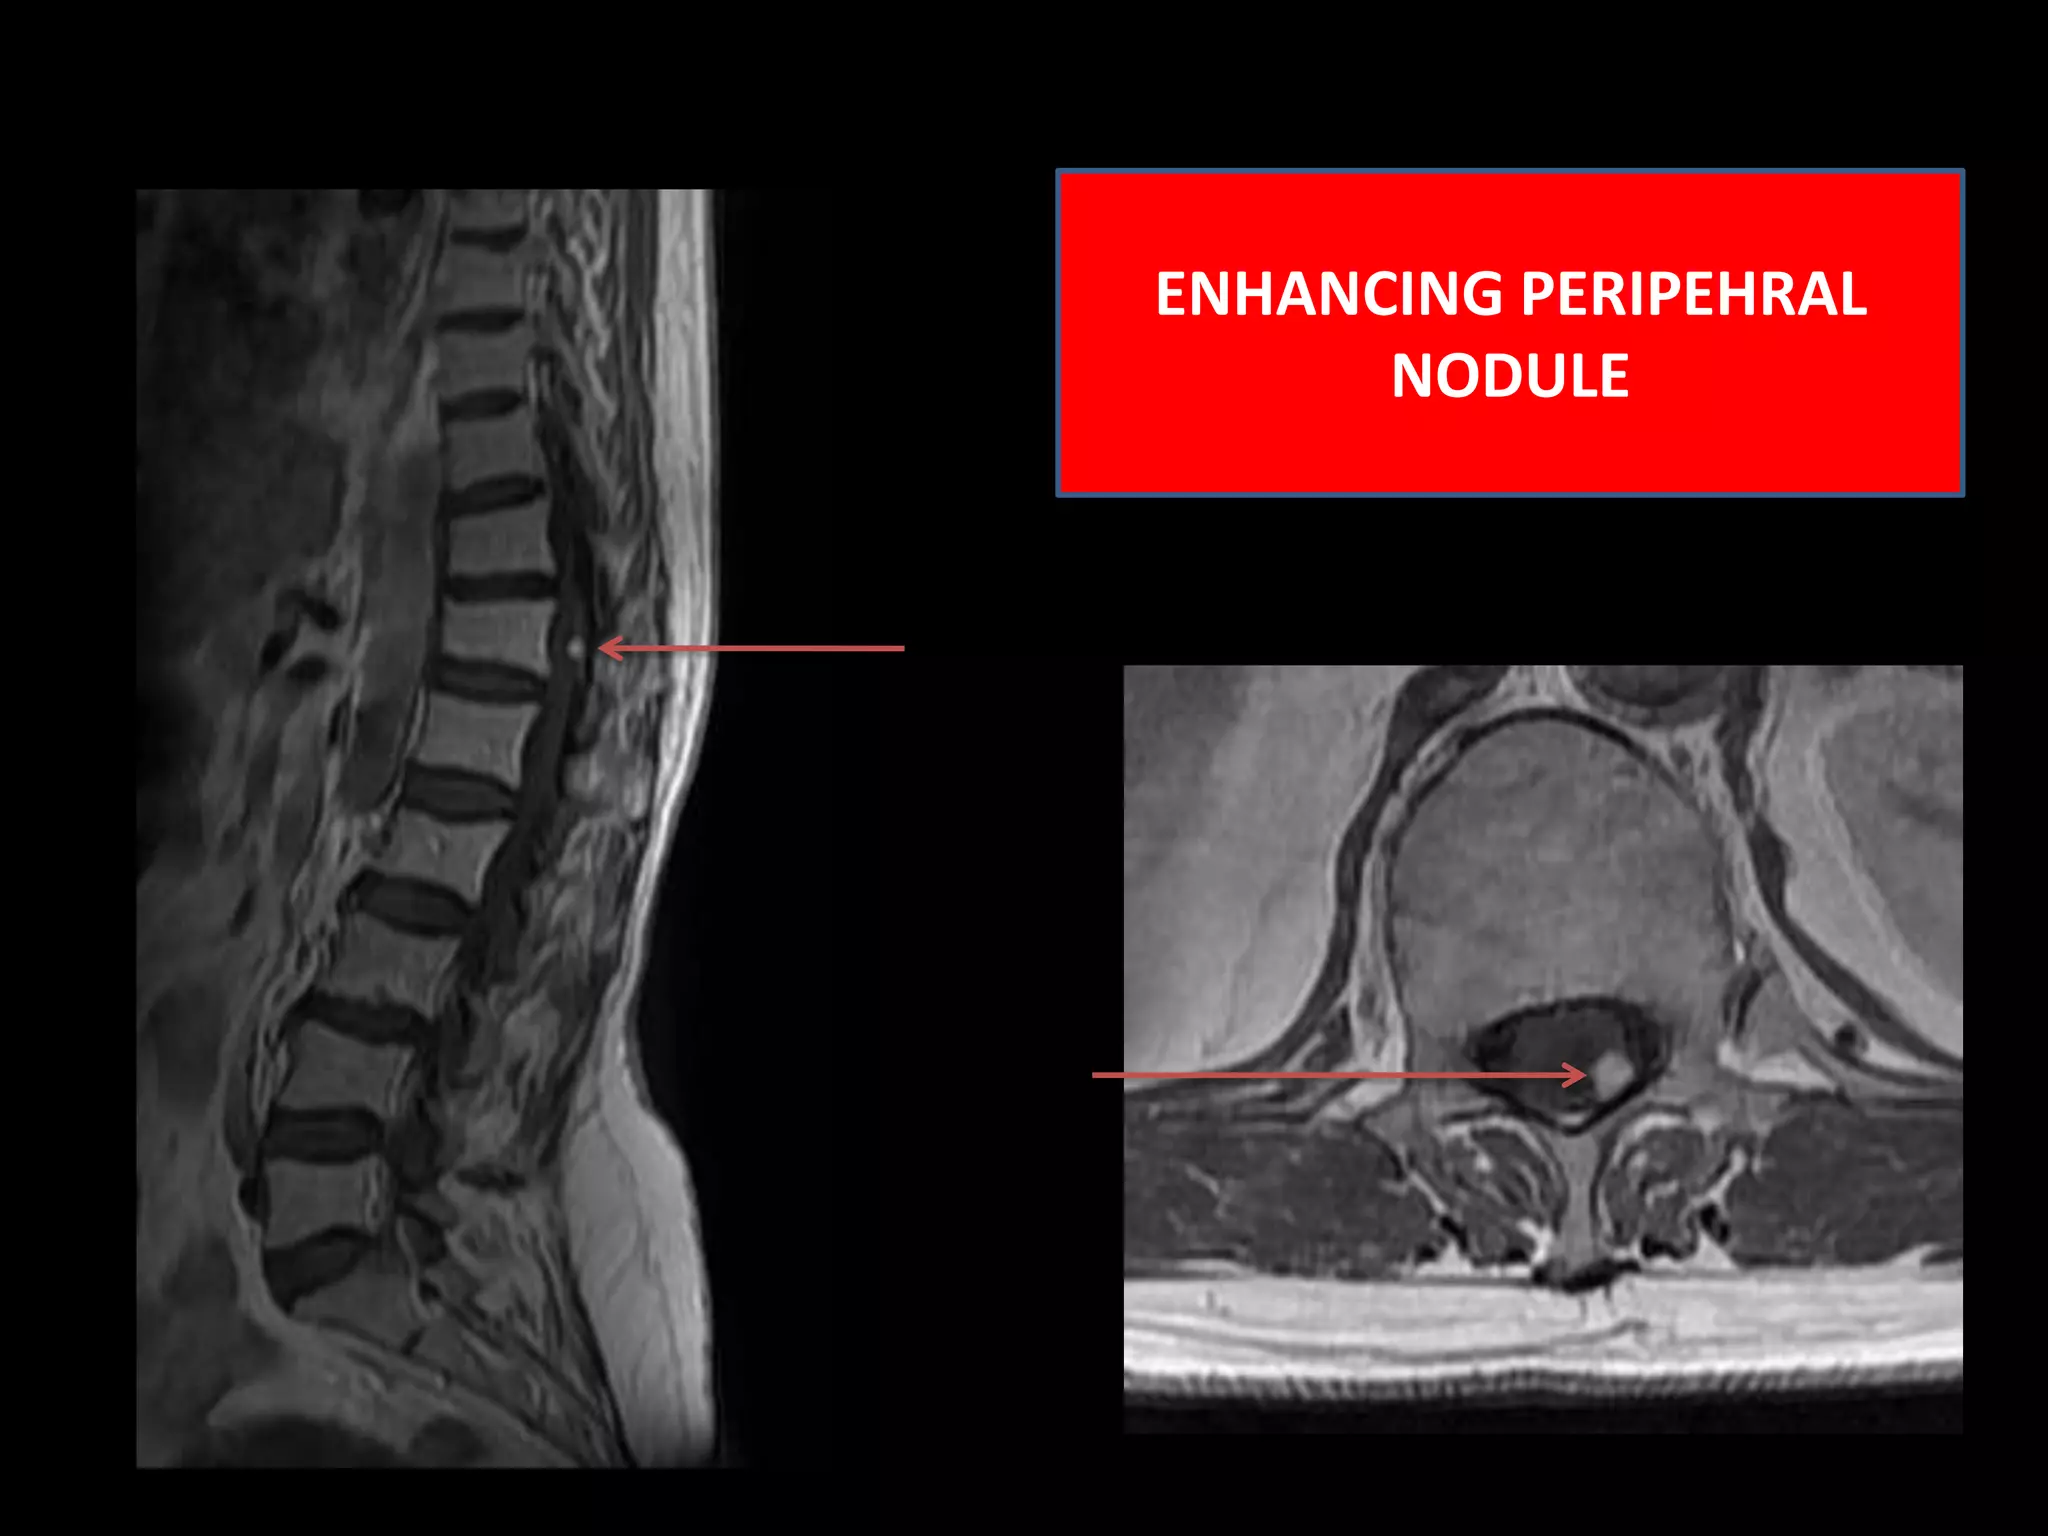

Case 158 Year old female with sensory and motor complaints pertaining to lower extremity with worsening for last one year. MR Images – Intramedullary cystic lesion ( size 28mmx 08mmx 08mm ) with septations and solitary intensely enhancing tumor nodule is appreciated in the lower dorsal region.                                  Important negative findings are :No cap sign appreciated. No signal voids appreciated .No associated syrinx .No Intratumoral cysts /Peritumoral cysts .No pathological enhancement elsewhere in the tumor.

INTENSLY  ENHANCING PERIPHERAL NODULE

ENHANCING PERIPEHRAL NODULE

Case 158 Yearold female with sensory and motor complaints pertaining to lower extremity with worsening for last one year. MR Images – Intramedullary cystic lesion ( size 28mmx 08mmx 08mm ) with septations and solitary intensely enhancing tumor nodule is appreciated in the lower dorsal region. Important negative findings are :No cap sign appreciated. No signal voids appreciated .No associated syrinx .No Intratumoral cysts /Peritumoral cysts .No pathological enhancement elsewhere in the tumor.

INTENSLY ENHANCINGPERIPHERAL NODULE